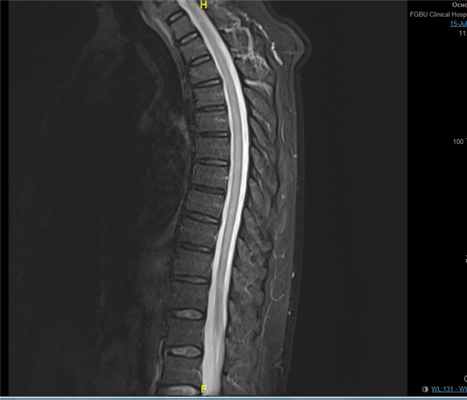

МРТ при миелите

Важное значение для прогноза имеет диагностика миелита и миеломаляции. Поперечный миелит относится к заболеваниям, характеризующимся быстрым развитием симптомов поражения спинного мозга. На МРТ в острой стадии может отмечаться некоторое утолщение спинного мозга в размерах с определением интрамедуллярно расположенной области повышения сигнала на Т2-взвешенных МРТ, захватывающего обычно несколько сегментов спинного мозга. В поздней стадии процесса МРТ выявляет нисходящую атрофию спинного мозга

Рис. 1. Магнитно-резонансная томография грудного отдела позвоночника без

контрастного усиления. А – сагиттальный срез в режиме T2 STIG. Б – аксиальный срез (линия среза указана на сагиттальном срезе), программа T2 tra. Стрелками указаны очаги поражения СМ

Пациент Л., 58 лет, перенес новую коронавирусную инфекцию с 09.04 по 20. 04.20., мазок от 20.04 отрицательный. После стал отмечать онемение в ногах, похолодание ног, в дальнейшем - постепенное нарастание слабости в нижних конечностях. 30.06 в связи с выраженной слабостью в ногах вызвал врача. Симптоматика была расценена как проявления дорсопатии, назначенное лечение (миорелаксанты, НПВС) без эффекта. 04.07.20 по 03.07.20 был госпитализирован в нейрореанимацию городского стационара, далее переведён в неврологическое отделение. Выполнялась люмбальная пункция, КТ головного мозга - без патологии. Состояние расценено как хроническая воспалительная демиелинизирующая полирадикулоневропатия. 13.07.2020 для дальнейшего обследования и лечения переведен в неврологическое отделение КБ № 1. При первичном осмотре в неврологическом статусе обращал внимание нижний вялый парапарез до плегии, снижение мышечного тонуса в нижних конечностях, неубедительные нарушения чувствительности с уровня Th10-Th11 по проводниковому типу. Проводились обследования: ЭНМГ – данных за поражение периферических нервов не получено, МРТ грудного отдела позвоночника: выявлен диффузный миелит, МРТ поясничного отдела позвоночника: признаки миелита. Пациент был консультирован нейрохирургом: диффузный миелит, вероятнее всего, вирусной (коронавирусной),этиологии. Нейрохирургическое лечение не показано. Консультирован инфекционистом: диффузный миелит, вероятнее всего, вирусной (коронавирусной),этиологии. Проводилась пульс-терапия Солу Медролом 1000 мг №7, антибактериальная терапия Меронемом, комплексная сосудисто-метаболическая терапия. Вопреки ожиданиям, на фоне проводимой терапии состояние и самочувствие пациента без существенной динамики в неврологическом статусе. При контрольном МРТ от 27.07.20 - отрицательная динамика в виде повышения неоднородности МР сигнала (увеличения объема облаковидных участков гиперинтенсивного МР сигнала на Т2, STIR ВИ) от спинного мозга на всем протяжении. Был начат курс плазмафереза. В дальнейшем, пациент продолжил терапию в отделении неврологии с палатами реабилитации. Выполнялась МРТ головного мозга, шейного отдела позвоночника, грудного отдела позвоночника с контрастированием - накопления контраста не было. 06.08.2020 г. пациент был выписан с грубым неврологическим дефицитом (нижняя параплегия, тазовые нарушения) с рекомендациями продолжить поддерживающую гормонотерапию на амбулаторном этапе.